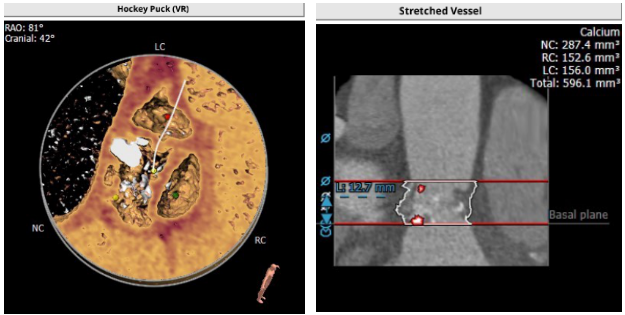

解剖结构

主动脉根部解剖动态图:

主动脉根部解剖:

血管入路解剖: